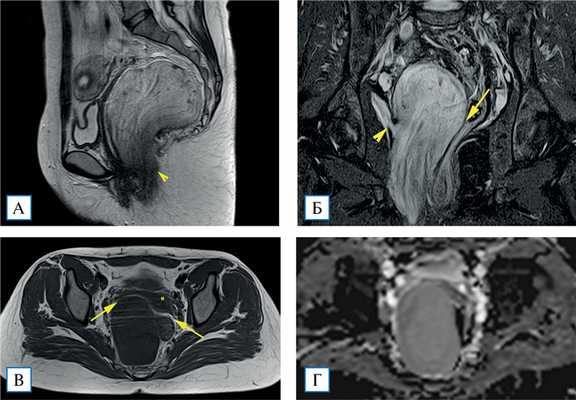

На 4-й день госпитализации выполнено МР-исследование: в малом тазу справа определяется объемное образование размером 70×70×145 мм с четким наружным контуром. На Т2-ВИ МР-сигнал по интенсивности выше, чем от миометрия, но ниже, чем от жидкости. Структура неоднородная за счет тонких беспорядочных протяженных волокнистых включений. На Т1-ВИ опухоль однородно гипоинтенсивная. Жироподобных включений, участков выпадения МР-сигнала, соответствующих кальцинатам, не прослеживалось. При получении диффузионно-взвешенных изображений данных за ограничение диффузии молекул воды не отмечено. Опухоль оттесняет в стороны прилежащие органы малого таза без признаков их инвазии. Нижний полюс опухоли выглядит нечетким, распространяется к m. levator ani (мышца, поднимающая задний проход) справа и в клетчатку правой седалищно- анальной ямки, инфильтрируя их (рис. 2).

Рис. 2. МР-томограммы малого таза, Т2-ВИ в сагиттальной плоскости (А), Т2-ВИ с подавлением сигнала от жира в корональной плоскости (Б), Т1-ВИ в аксиальной плоскости (В), изображение с картой исчисляемого коэффициента диффузии в аксиальной плоскости (Г)

Примечание. Объемное образование вовлекает m. levator ani справа (А, Б, наконечники стрелок). Между образованием, маткой, придатками матки справа и прямой кишкой прослеживаются жировые прослойки (Б, В, стрелки). Исчисляемый коэффициент диффузии от образования составляет около 2300 мм/с 2 (Г).